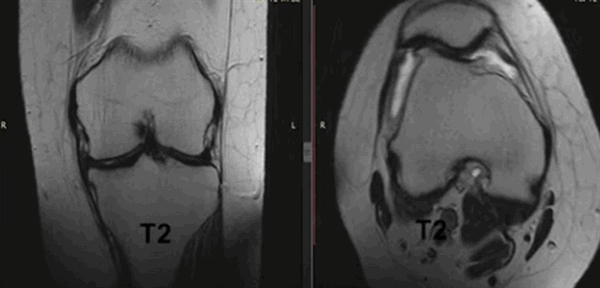

На снимке - разрыв крестообразной связки и мениска вследствие травмы колена

Для диагностики важна еще и форма мениска. В норме он в определенной плоскости имеет форму бабочки. Любые отклонения могут указывать на возможный разрыв.

Варианты просмотра коленного сустава при МР-сканировании в разных проекциях (Т2 ВИ)